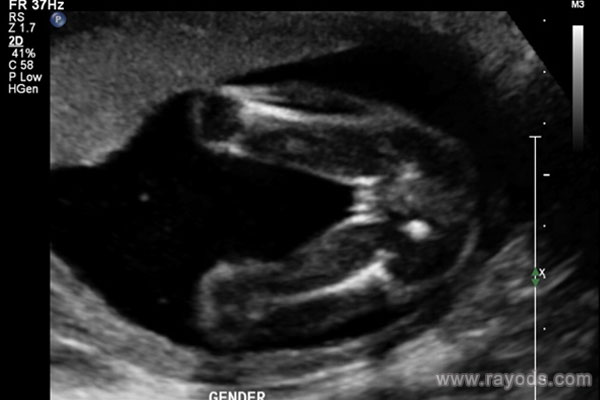

(女宝腿部间性别特征)

如果是男孩会看到凸起的一坨,有的还会看到上面的小尖尖,女孩则是圆圆的一坨,有点鼓包样。30周的时候男孩女孩胎儿的生殖器已经很好区分了,一般的分辨依据就是根据其外生殖器结构,男孩的要更明显得多。在30周之前男孩生殖器这里一般会有圆球或者亮点,女孩胎儿在30周的时候看双腿间的话会有白线,一般都是三条白线,代表的是女孩的大小***。

因此,如果大家有幸看到胎儿腿部间有凸出的,就像是小乌龟一样的,那十有八九怀的是男孩,反之如果腿部间平平的甚至还会看到三条白线的话一般就是女孩了。当然,提醒一下各位妈妈们,这个时候胎儿胎动活跃,角度和体位也会随时变换,有时候很容易将手指或者脐带弄混淆,这个时候就要看生殖器的反光和亮点来区分了。